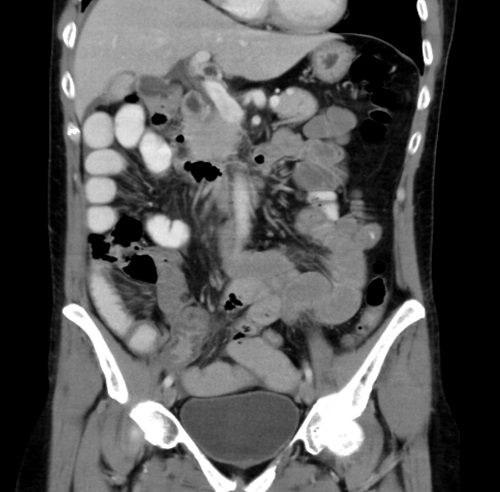

Como estudio complementario se solicitó un laboratorio que evidencia leucocitosis (13 000 glóbulos blancos). Además, se realizó una ecografía abdominal que informa distensión de asas de delgado asociado a líquido libre interasas, por lo que se solicitó una tomografía abdominopélvica con contraste intravenoso. Esta evidenció distensión de asas del delgado con contenido líquido en su interior, edema submucoso en íleon distal y líquido libre en pelvis (Fig. 1).

Figura 1.Tomografía computarizada abdominopélvica que evidencia transición asa fina-asa gruesa en íleon distal.